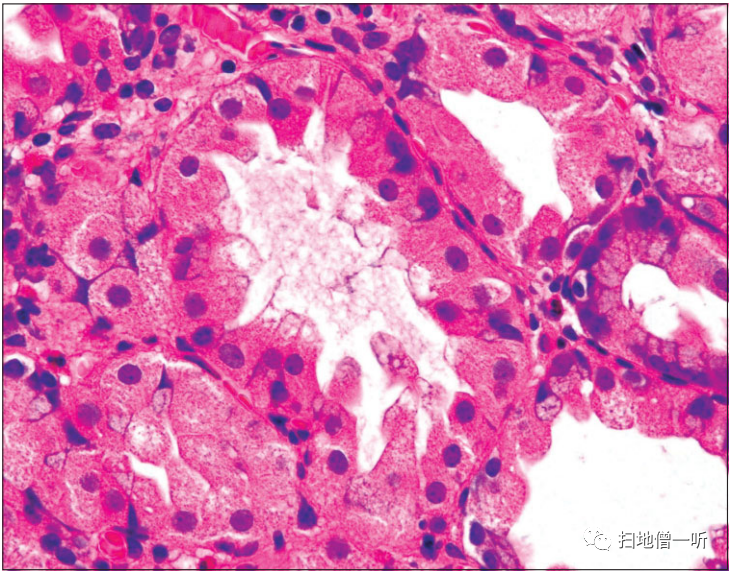

【内镜术后的瘢痕性增生性息肉】

患者70多岁,男性,内镜治疗后投用PPI,血清胃泌素显示出612.9 pg/ml的高值。投用PPI后,在溃疡瘢痕部发生增生性息肉。

▲在增生性上皮,发现了胃泌素受体。

〔Takamura A, et al. High expression of gastrin receptor protein in injured mucosa of Helicobacter pylori-positive gastritis. Dig Dis Sci 58:634-640, 2013より転載〕.

PPI抑制胃酸分泌,诱导继发性高胃泌素血症。在日本的队列研究中,报道了长期使用PPI通过高胃泌素血症与胃增生性息肉的发生有关。以前,笔者等人用免疫组织化学的方法证明了胃泌素受体在胃肿瘤内镜治疗后瘢痕产生的增生性粘膜上皮中表达。此现象对于说明使用PPI引起的增生性息肉的增大是合理的机制。